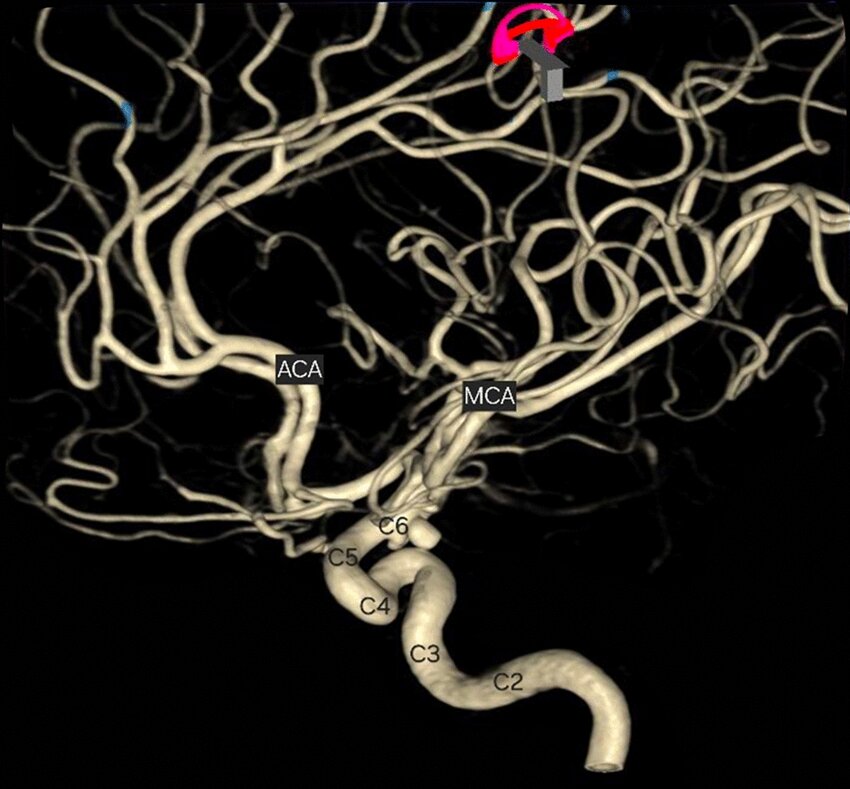

- MRI 可提供腦部及其血管的詳細影像,從而評估中風類型。

- MRI 亦可顯示缺血性中風時血管阻塞的部位和範圍,或出血性中風時出血的部位和範圍,從而提供選擇合適治療方案的指導。